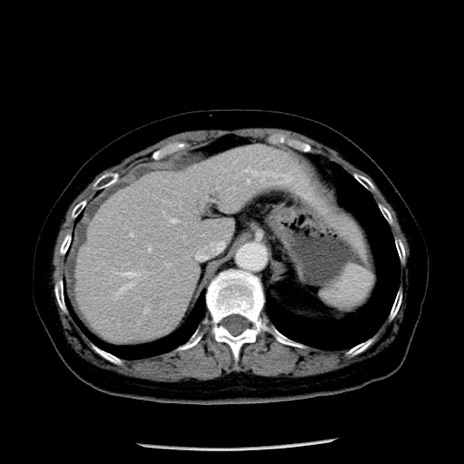

冠状断像

【症例】70歳代女性

【主訴】腹痛、嘔吐

【現病歴】15時間程前(昨晩)より腹痛あり。今朝になっても症状の改善なく、嘔吐あり。腹痛も増悪あり、救急外来受診。

【既往歴】子宮癌全摘術後

【身体所見】意識清明、BP 121/72mmHg、P 74bpm、SpO2 100%(RA)、腹部:平坦・軟、腸雑音ほぼ聴取せず。下腹部・心窩部・臍左上に圧痛あり。反跳痛なし。

【データ】WBC 10600、CRP 0.15